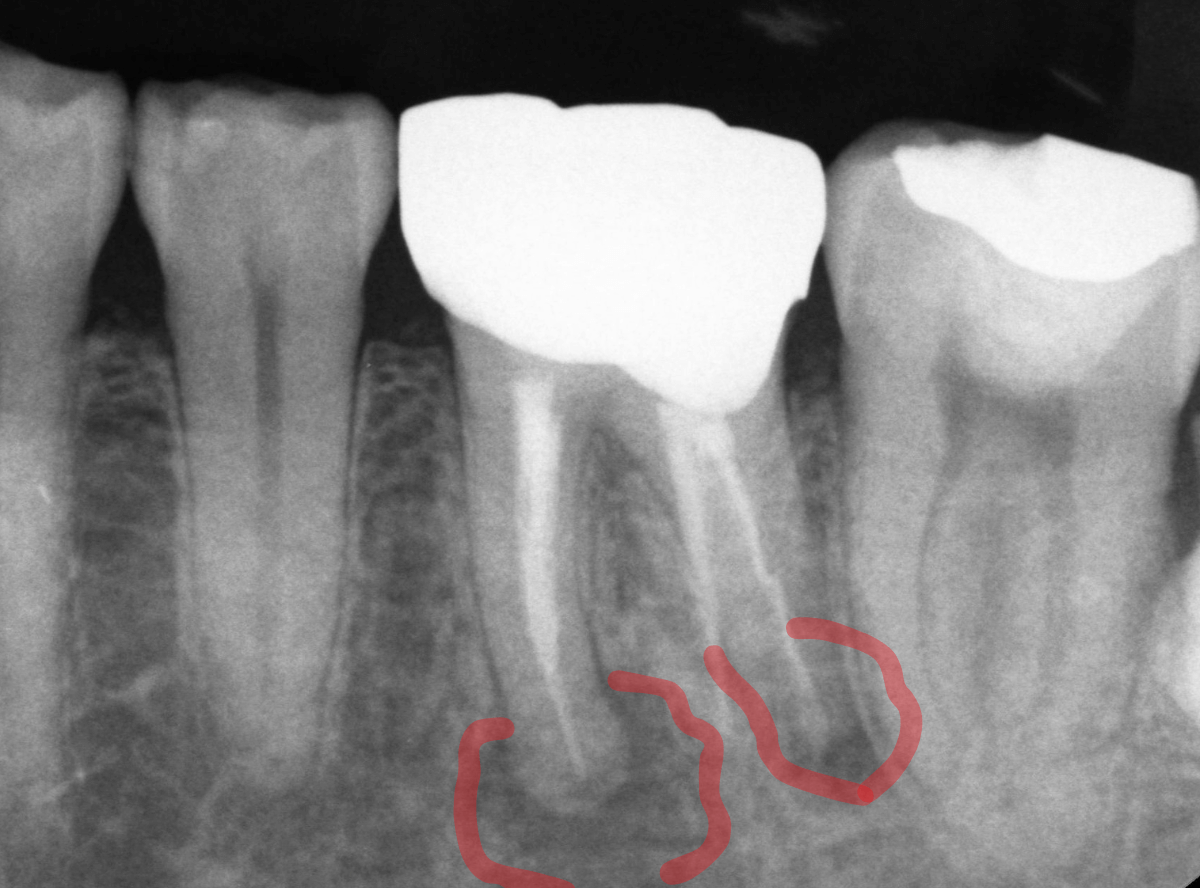

根尖病巣の大きさや炎症の程度はレントゲン写真でかなり判断できますが、必ずしも症状と一致しない事が多いのもやっかいなところで、「根管治療は難しい」とい言われる理由の一つです。

Aあります。 レントゲンで大きな透過像(根尖病変)が認められると、自覚症状がなくても治療を検討します。